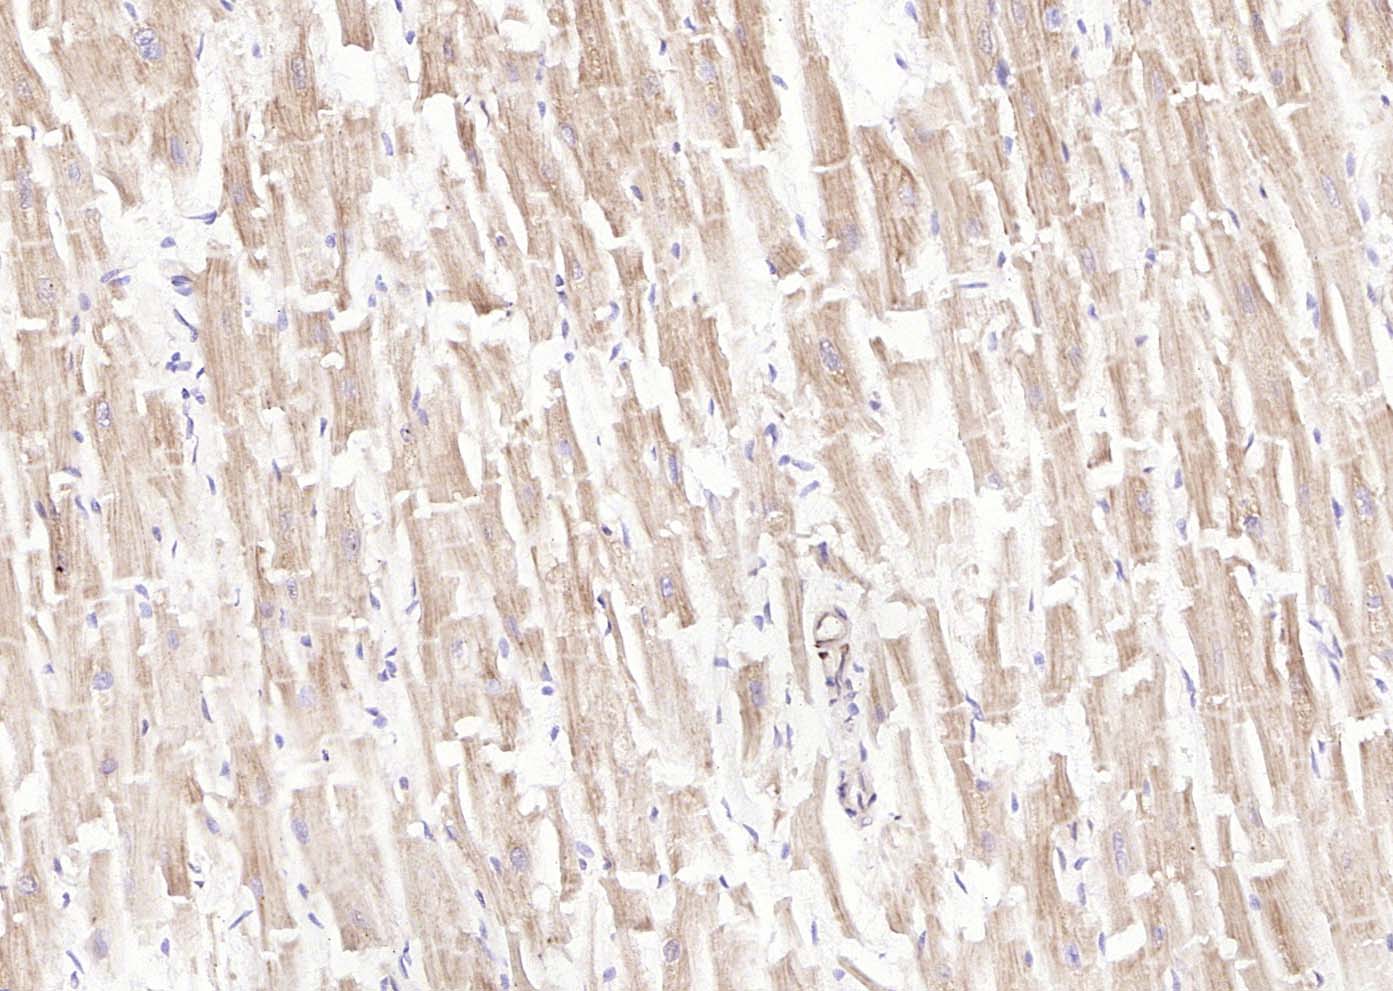

Paraformaldehyde-fixed, paraffin embedded (human heart); Antigen retrieval by boiling in sodium citrate buffer (pH6.0) for 15min; Block endogenous peroxidase by 3% hydrogen peroxide for 20 minutes; Blocking buffer (normal goat serum) at 37°C for 30min; Antibody incubation with (LIFR) Polyclonal Antibody, Unconjugated (bs-25592R) at 1:200 overnight at 4°C, followed by operating according to SP Kit(Rabbit) (sp-0023) instructionsand DAB staining.